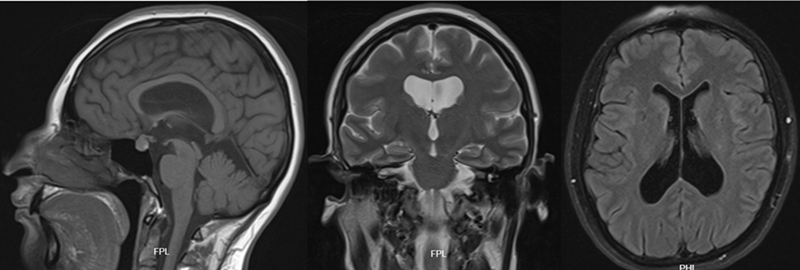

Introduction  Hydrocephalus is a condition characterized by the abnormal accumulation of cerebrospinal fluid within the brain's ventricular system. It can stem from obstructive and nonobstructive causes. Pregnancy introduces physiopathological changes that may heighten the risk of developing or worsening symptomatic hydrocephalus. Nevertheless, comprehensive reports on this aspect, especially regarding surgical interventions, remain scarce. Case Report  A young woman with a history of recurrent headaches experienced a worsening of her symptoms at the onset of her pregnancy. A magnetic resonance imaging (MRI) in the first trimester revealed increased ventricular dilation, indicating an obstructive cause due to aqueduct stenosis. During a neurosurgical board meeting, treatment options were discussed, considering the identifiable obstruction, the heightened intra-abdominal pressure associated with pregnancy, and the risk of ventricular shunt dysfunction. The patient underwent an endoscopic third ventriculostomy (ETV) without complications, leading to both symptom relief and a successful conclusion to the pregnancy. Discussion  Neurosurgical procedures in pregnant women are uncommon due to the increased risks to both the mother and the fetus. However, when performed by a qualified multidisciplinary team, they can lead to positive outcomes. In cases of hydrocephalus during pregnancy, ETV appears to be a viable alternative for surgical intervention, particularly when hydrocephalus becomes symptomatic and an obstructive cause is identified, whether in patients with existing shunts or those with newly developed hydrocephalus.

Abstract Image